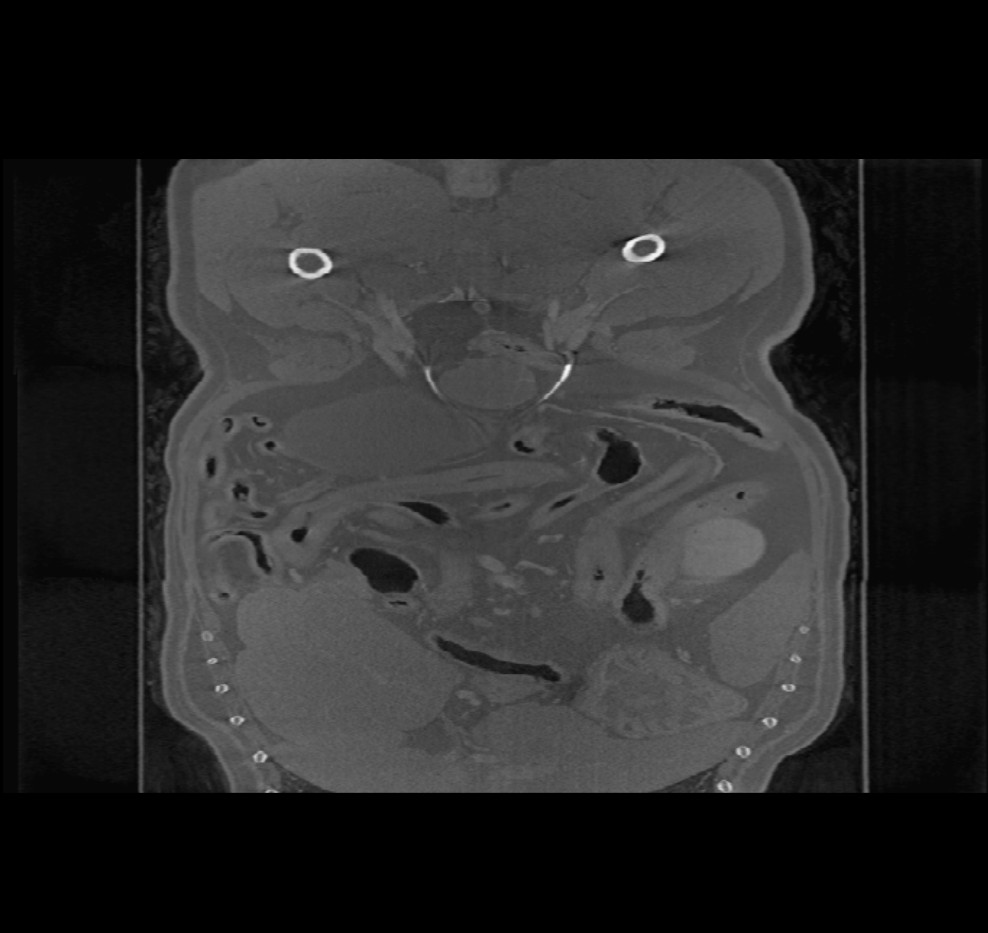

When opening volumetric DICOM images in the Viewer (CT and MR modality), an additional menu is available in the top toolbar titled Image Planes. Change the orientation of the image by choosing one of three available planes (Axial, Coronal,

and Sagittal).

The chosen plane affects the position and orientation of the CT/MR slices and their reconstruction on the 2D plane.